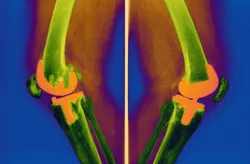

Knee replacement is one of the most common surgical procedures in the U.S., and the DePuy knee replacement system has been one of the more popular options. However, after a known problem with the balseal was brought to light, DePuy recalled components of the Attune knee replacement device in 2015.

The DePuy knee replacement is one of several such devices linked with serious component problems. With the Attune, the issue was the balseal; with other knee systems it’s the tibial plate. No matter the issue, however, complications from a DePuy knee replacement or similar implant have necessitated patients to undergo revision surgery to alleviate the issue.

The DePuy knee replacement system is a popular knee implant option in the U.S. However, although the DePuy knee replacement was meant to reduce the time required for recovery, it has unfortunately been linked with some severe issues that can have lasting effects.